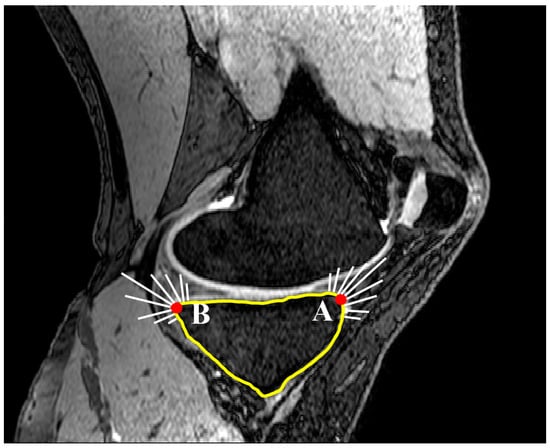

2.1. Medial and Lateral Tibial Slope Measurement Methodology

2.3. Concavity Zone